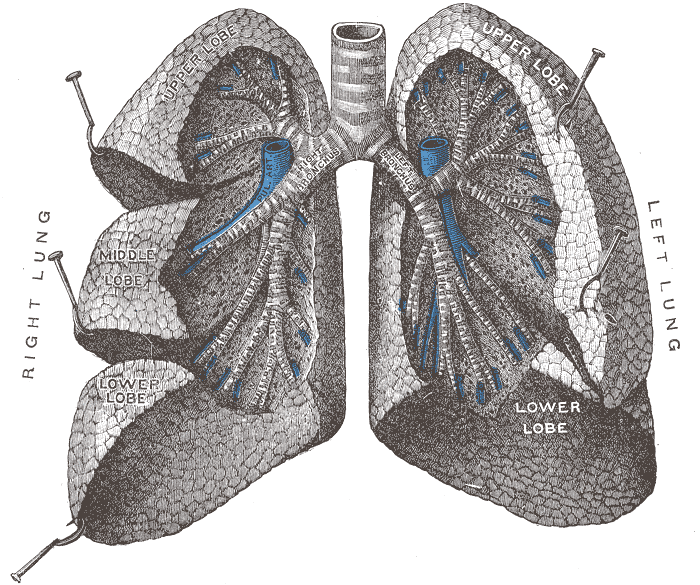

- Figure 1. Lung anatomy53

- The trachea branches into the two primary bronchi at the hilum, which then divide into bronchioles. These subsequently branch off into the alveolar ducts and then the alveoli themselves.

- Each lung is enclosed within visceral pleura, dividing the right lung into three lobes and the left lung into two. These structures all lie within the parietal pleura adherent to the inner wall of the rib cage. The pleural cavity in between these two layers contains a lubricating pleural fluid.

- Each bronchopulmonary segment carries its own blood supply.

- The pulmonary interstitium refers to the collection of support tissues extending throughout both lungs. It consists of the alveolar epithelium, pulmonary capillary epithelium, basement membrane, perivascular, and perilymphatic tissues.